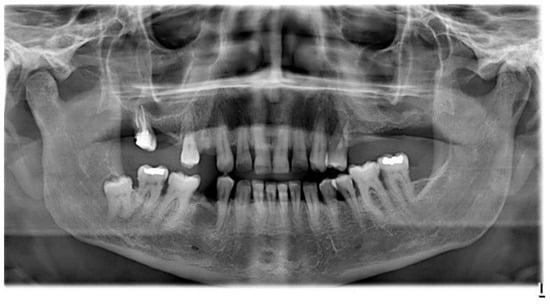

2. Case Report

The subject involved in this clinical study was a healthy woman, 54 years old. The request of this patient was to improve her mouth both functionally and aesthetically, which was altered because of the partial edentulism (Kennedy Class II). She asked to avoid any invasive surgery. During the anamnesis, she declared not to be affected by any systemic pathology (e.g., diabetes, hypercholesterolemia or hypertension). She also declared not to be affected by an allergy to any medication or similar drugs; she declared not to be subjected to any pharmacologic treatment except some analgesic therapy to treat sporadic headaches. The patient claimed to smoke 20 cigarettes a day for more than 20 years. The next step was to perform an objective examination, associated with a series of intraoral pictures (Figure 1, Figure 2, Figure 3, Figure 4 and Figure 5) and to the analysis of a radiographic exam (orthopantomography, Figure 6) that was acquired 10 months earlier when the same subject underwent the therapy and the teeth extraction 4.7–4.8. The objective examination showed poor oral hygiene, with plaque accumulation as well as the presence of many pigmentations due to excessive smoking. The radiography showed bilateral bone atrophy together with periodontal damage for most of the residual dental elements. These conditions represented a limitation to the insertion of implants for a fixed prosthesis.

Figure 6. Orthopantomography.